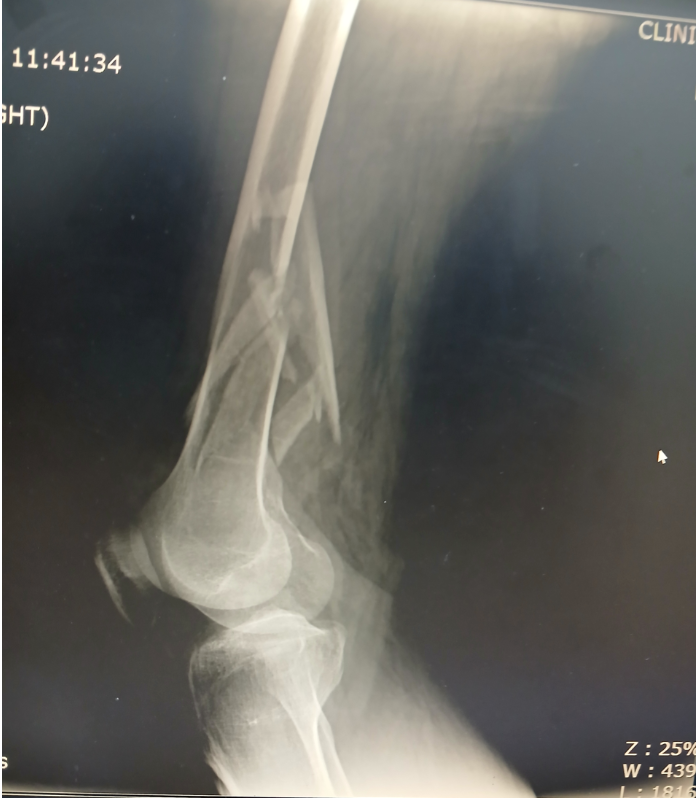

12月21日,我司分别与客户本人及旅行社建立沟通,陆续搜集到了更多出险信息,得知12月20日客户在旅行途中因路滑不慎摔倒,疼痛剧烈随即被导游送医就诊。经医院检查诊断为右股骨远端粉碎性骨折,建议住院手术治疗。客户与家属商讨后同意遵医嘱治疗。